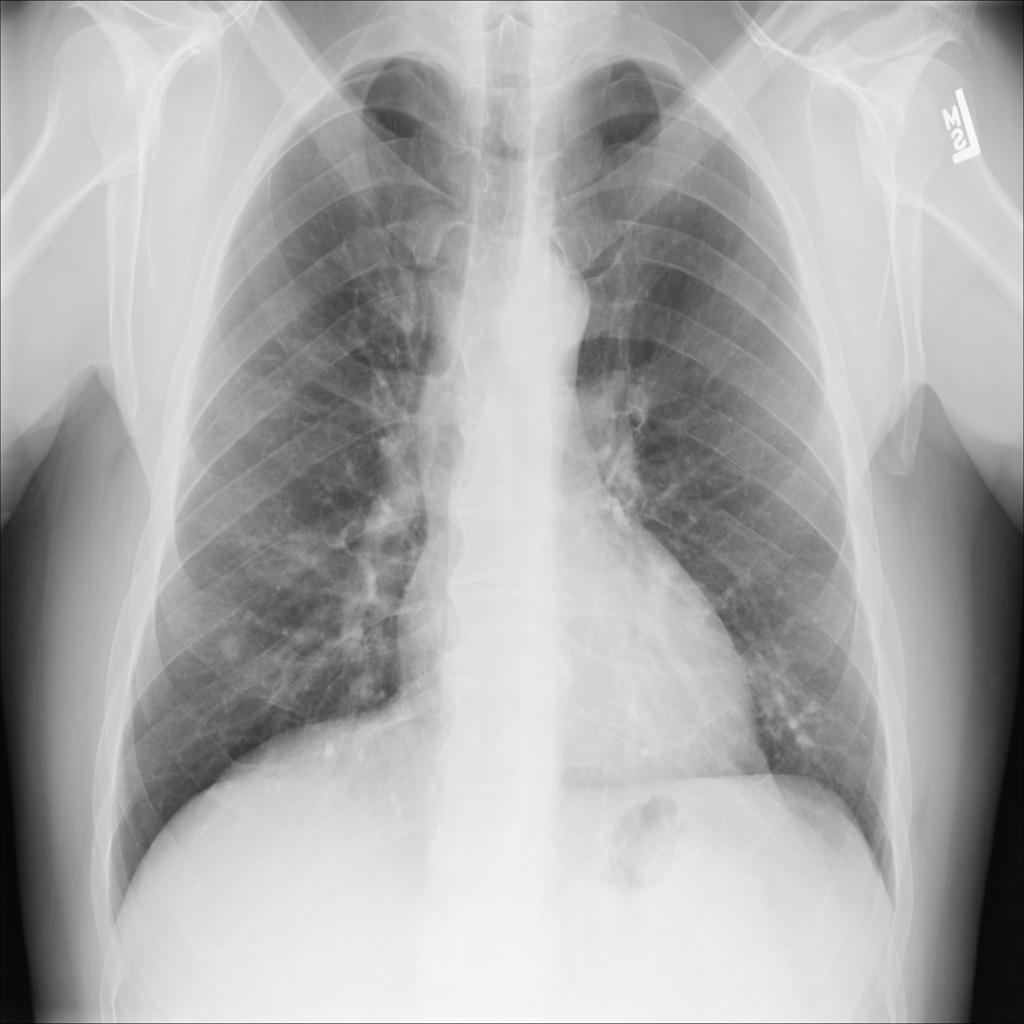

Nodule

A nodule is a small rounded opacity in the lung or chest field. It is a descriptive imaging finding that can be benign or more concerning depending on size, appearance, and context.

Showing up to 90 reference images for Nodule.

PAT-250B · IMG-000Nodule

PAT-250B · IMG-000

PA